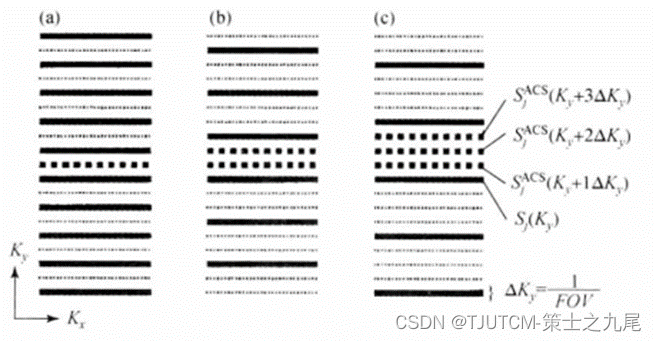

实线表示测量的K空间行,小点线表示缺失的K空间行,在中间区域额外测量的奈奎斯特采样行(大点线)即ACS行用来确定合成缺失行(小点线)的权重因子,相位编码在竖直方向

((a)R=2,(b)R=3,©R=4)

这些额外采集的ACS行是用传统相位编码梯度编码的,这些参考行SjACS和通常SMASH信号行之间的关系可用来确定线性权重因子aj,p

AUTO-SMASH和VD-AUTO-SMASH的K空间ACS行数据重建机制,从多线圈测量行数据合成全视野的符合校正行数据(此例中采集的4行数据用于拟合出覆盖全视野的复合数据)。

GRAPPA的K空间ACS行数据重建机制,阵列中各个线圈中采集的多块测量行被拟合到阵列中一个单线圈中采集的ACS行(此例中采集的4行数据用于拟合进4号线圈中一个单ACS行,各个圈代表在单一单线圈中采集的数据行)。